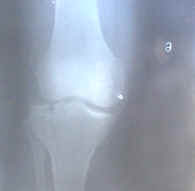

病例:李卫国

李卫国,男,出生于1973年3月23日,住万载县康乐镇坏城北路72号。于1999年7月9日下午从宜春乘货车回家,因车出事故跌伤左脚和左手,经撮片诊断左脚胫骨平台外侧纵行骨折,左手挠骨骨折,医院建议到大医院手术治疗。患者不同意去,当天来我处治疗,脚上贴药2张大号膏药,手上贴1张大号1张小号膏药。手上用药二次,20多天能用力自如。脚由于伤势重,折骨裂缝大,贴药10多天后肿基本全消,20多天后就能用拐杖行走。现在患者走路时与原来一样。